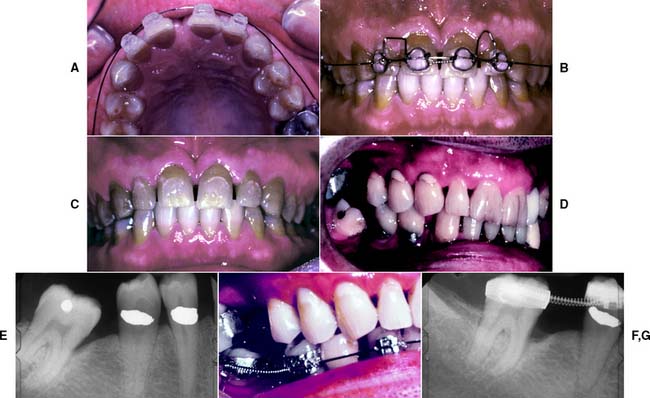

For tipping or extruding a single anterior tooth, acid-etch brackets can be used with a multistrand elastic wire ligated in place to attain the desired position. When any anterior tooth is moved, however, the amount of labial bone should be carefully evaluated and found to be adequate. Orthodontic treatment should also be considered when restorations are being used to correct a diastema. Often esthetics can be dramatically improved by distributing the space of a midline diastema around all the anterior teeth (Fig. 6-25A to C). A diagnostic waxing procedure will help determine the optimum tooth position. Uprighting a mesially tilted molar can be accomplished with a coil spring (see Fig. 6-25D to G), but the tooth should first be adjusted out of occlusion. A neglected crown preparation can be salvaged with a simple orthodontic appliance (Fig. 6-26). All orthodontic movement requires adequate anchorage so that inadvertent movement of other teeth is avoided.

Fig. 6-25 Orthodontic tooth movement as an adjunct to fixed prosthodontics. A to C, Minor tooth movement before correction of a diastema. D to G, A mesially tilted molar uprighted with a coil spring before the provision of a fixed dental prosthesis.